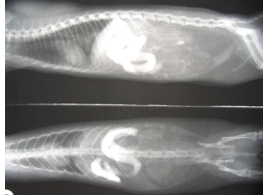

特に若いフェレットに多いのですが、それらのまぎらわしい異物は生涯を通じてフェレットのまわりには、置かないよう心がけましょう。自然界には、それらの異物は存在しませんから、フェレットが間違って、飲み込むことがあるからです。スポンジを飲みこんで、元気がなくなり、食欲不振となり、下痢をして、嘔吐をして、X線検査にて腸管の詰まりが証明され、腹部の開腹手術をして、取り出すという若いフェレットが、しばしば当病院に来院します。フェレットは特に音の出るおもちゃに興味があるようで、遊んでいて思わず飲み込んでしまうことがあります。

問題は、異物を飲んだという飼い主の訴えがない場合です。ほとんどが注意深い触診とX線撮影検査で発見されますが、訴えがないぶん発見が遅れると危険な状態となります。

しかし重要なことは、若いフェレットのお腹を触って何か固まり?がある状況で、開腹手術をするのは、医学的に少し無理があります。しなくてもいい手術をする可能性があるからです。また腸の詰まりは疑えても胃の異物は触診ではわからない場合があるからです。また腸の詰まりでも布やガーゼは触診では見つけ難いのです。あるのにわからない、ないものをあると間違い手術をする危険性があります。通常でも胃や腸には毛などが混入して詰まっているように思える場合があるし、いくらかは存在しているからです。最低限、X線検査が必要です。それも2方向の2枚以上が必要となります。超音波検査や、状況によってはバリウム造影検査が必要となる場合もあります。診断のプロセスは科学的に裏付けられた証拠の元に診断と治療を行います。これは人間の診断のプロセスと殆ど同じです。

| ▲バリウム造影検査にて上部胃腸管の閉塞が認められる。 | ▲詰まっていた布の塊。 |